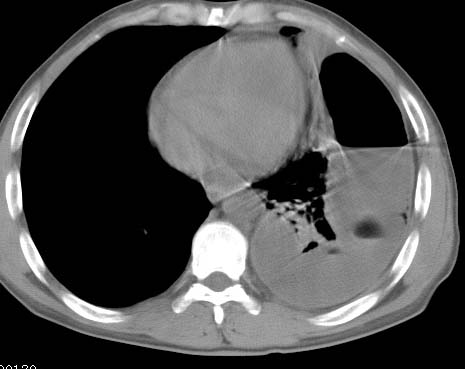

标题: CT10145:男性,30岁,活动后气促2月余.隔疝伴胸腔积液.右上肺结 [打印本页]

男性 病人 30岁,活动后气促2月余.隔疝伴胸腔积液.右上肺结核!

左侧胸腔积液,并胸腔内见多个含液 气组织,并相互重叠。影像特征很特殊,应该是“膈疝”。支持!

左侧膈疝,及左侧胸水,双上肺结核。

支持!左侧膈疝,左侧胸水,双上肺结核。

左侧胸腔包裹性液气胸未除。